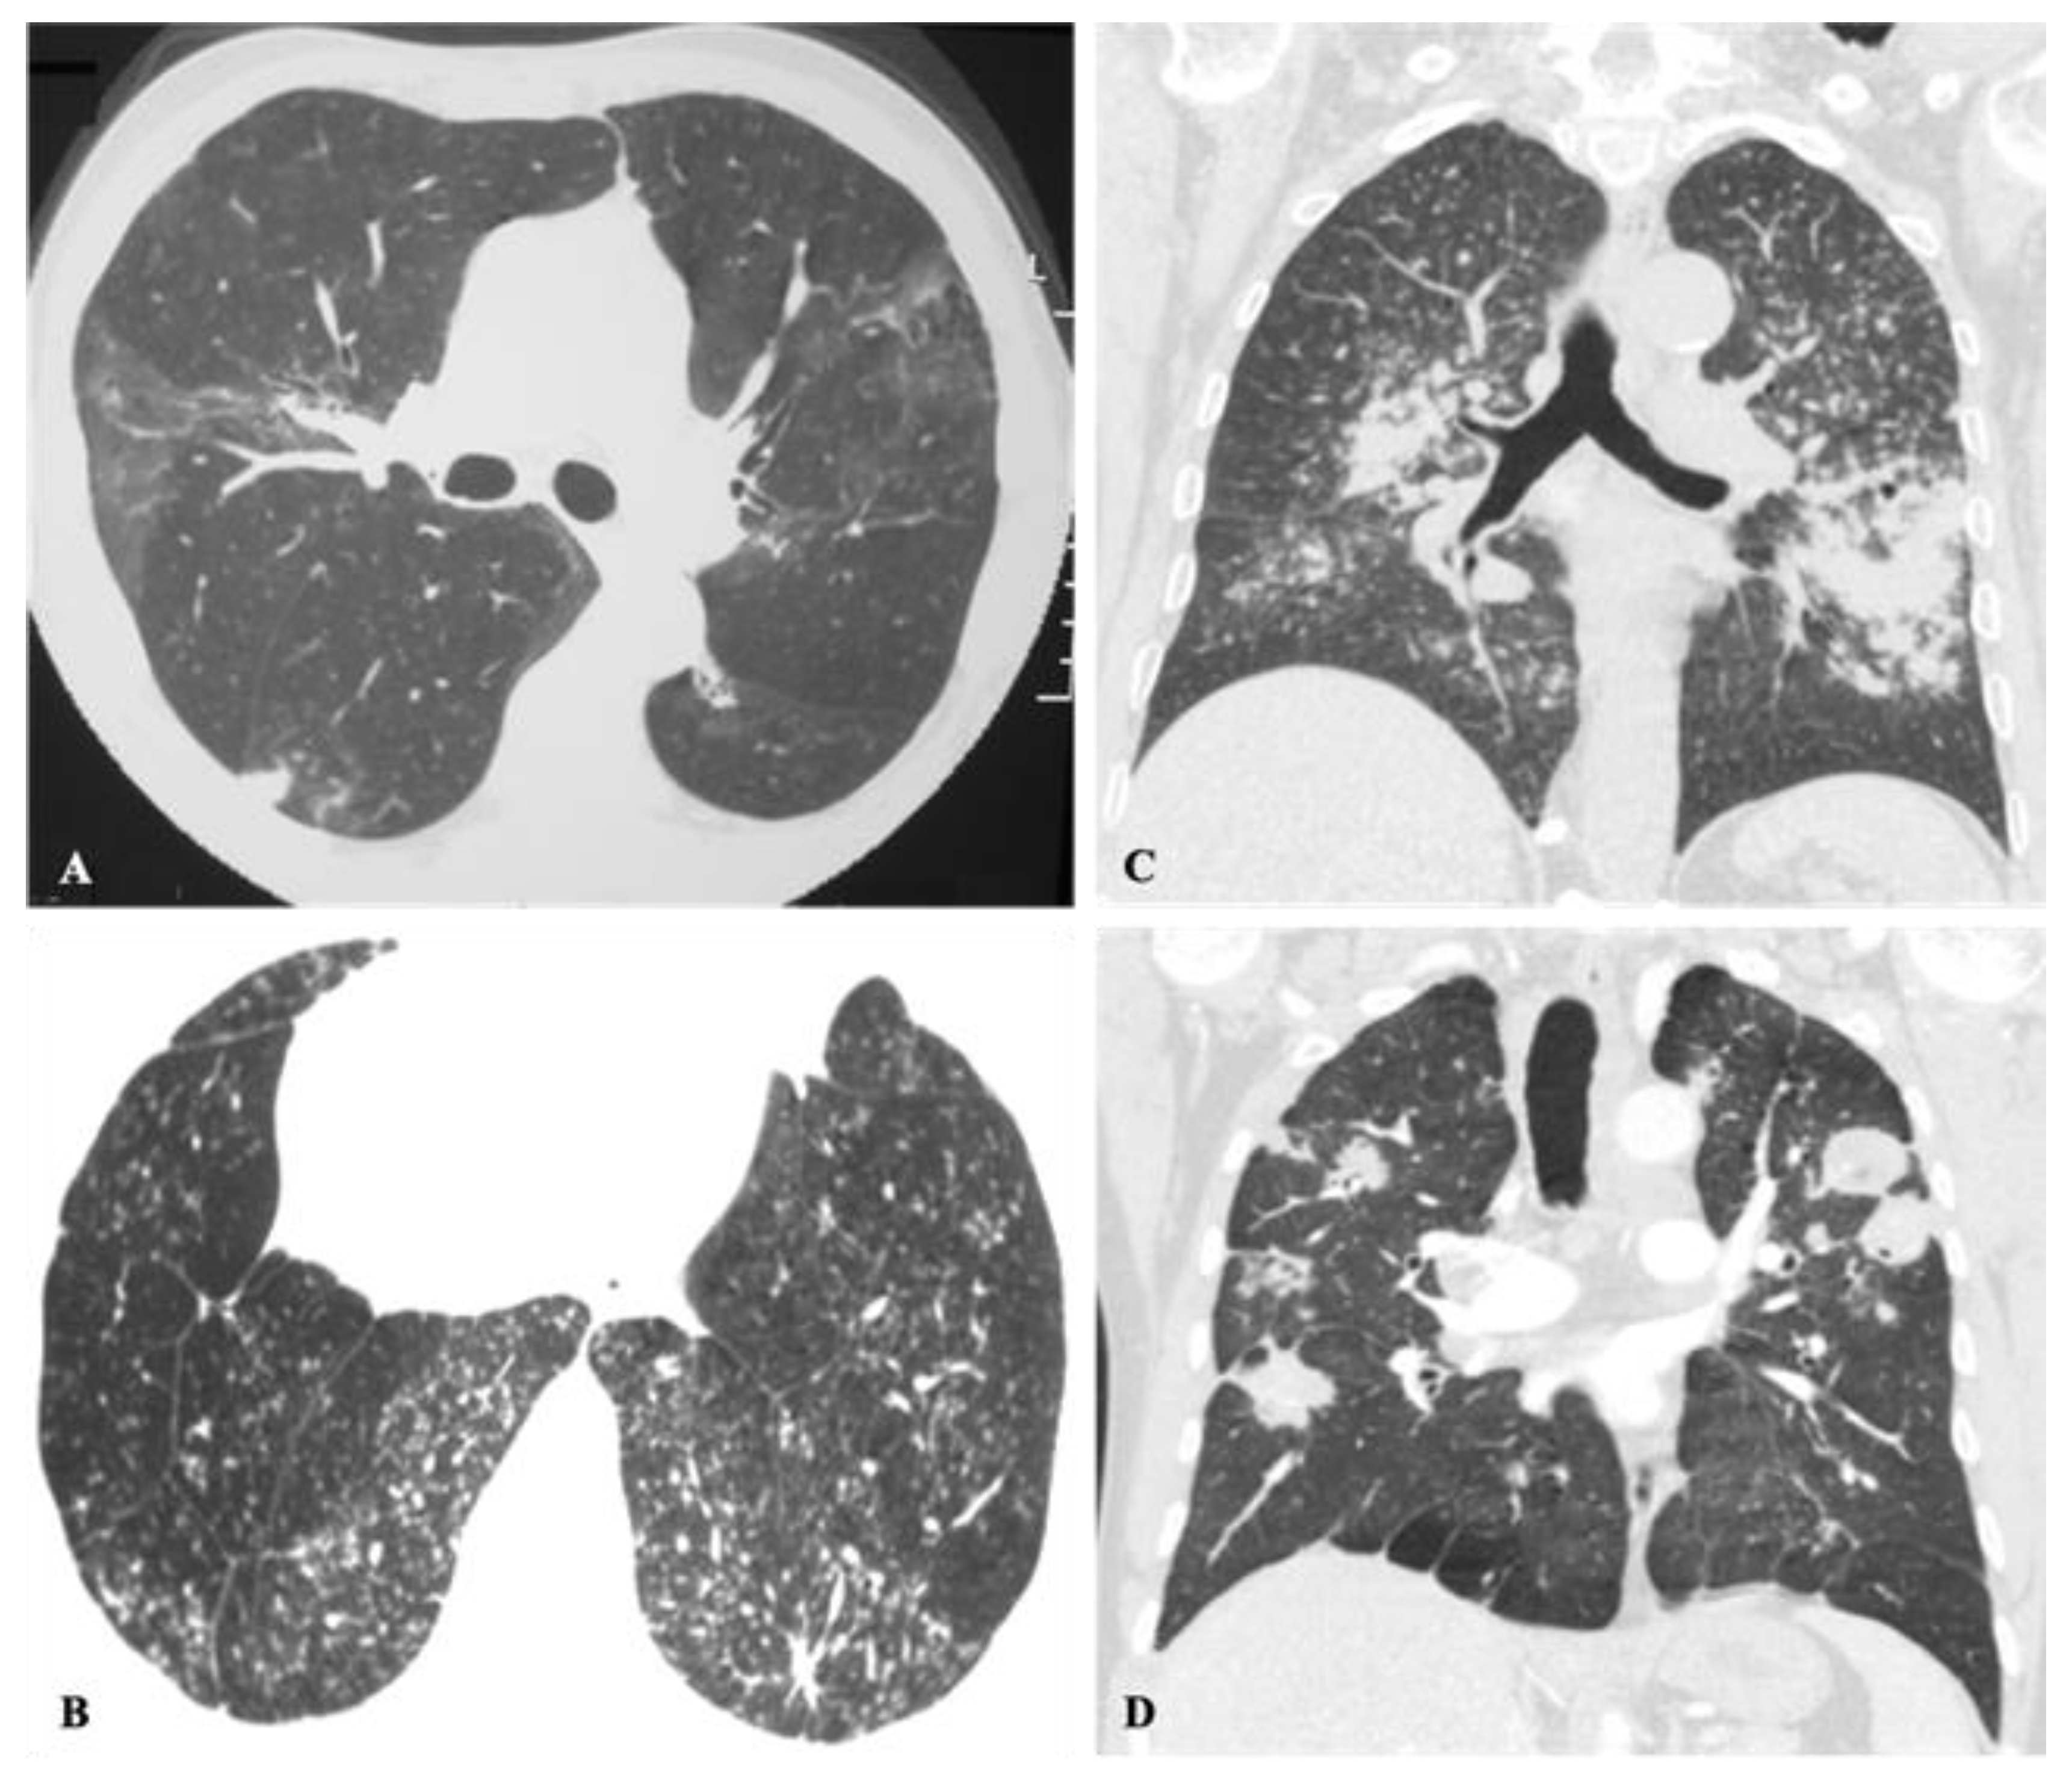

2.2. Non-Resolving Pneumonia

- Barreto, M.M.; Marchiori, E.; Amorim, V.B.; Zanetti, G.; Takayassu, T.C.; Escuissato, D.L.; Souza, A.S.; Rodrigues, R.S. Thoracic paracoccidioidomycosis: Radiographic and CT findings [published correction appears in Radiographics. Radiographics 2012, 32, 71–84. [Google Scholar] [CrossRef] [PubMed]

- Marchiori, E.; Valiante, P.M.; Mano, C.M.; Zanetti, G.; Escuissato, D.L.; Souza, A.S.; Capone, D. Paracoccidioidomycosis: High-resolution computed tomography-pathologic correlation. Eur. J. Radiol. 2011, 77, 80–84. [Google Scholar] [CrossRef]